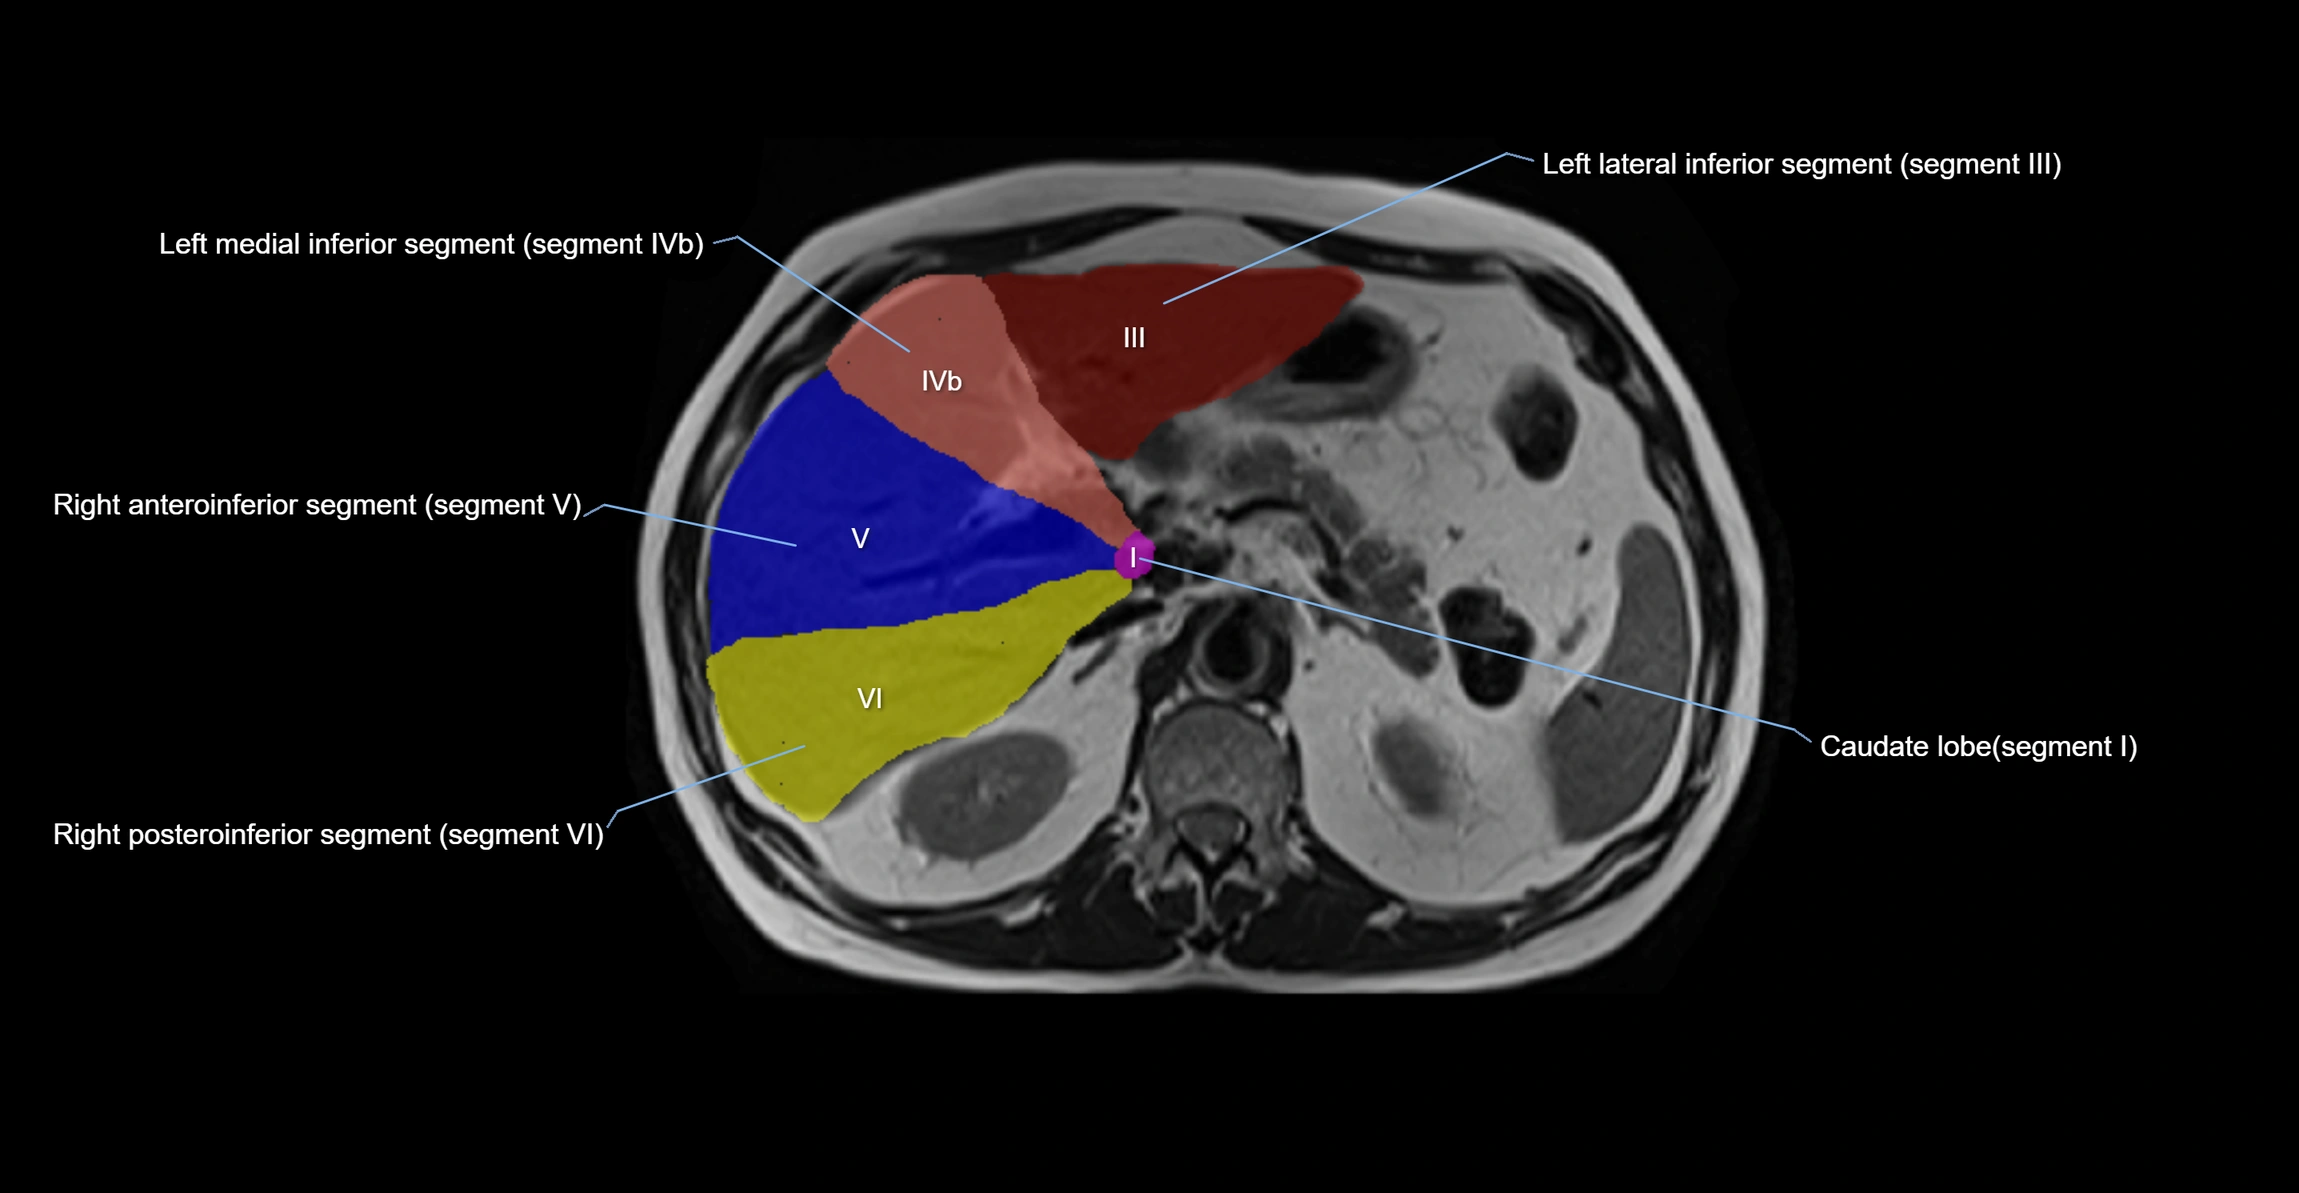

The caudate lobe of the liver is a distinct anatomical subdivision of the liver, designated as segment I in Couinaud’s classification. It lies on the posterior surface of the liver, between the fissure for the ligamentum venosum (left boundary) and the groove for the inferior vena cava (IVC) (right boundary). Superiorly, it is related to the posterior liver surface, and inferiorly it is separated from the left lobe by the porta hepatis.

The caudate lobe is unique because it receives dual portal venous and arterial inflow from both the right and left portal veins and hepatic arteries. It also has independent venous drainage directly into the IVC via multiple small hepatic veins, unlike other lobes that drain through the three main hepatic veins.

This anatomical autonomy makes the caudate lobe especially significant in liver surgery, transplantation, and hepatic venous outflow obstruction syndromes (e.g., Budd–Chiari syndrome). Enlargement of the caudate lobe is a characteristic imaging feature in chronic liver disease and cirrhosis.